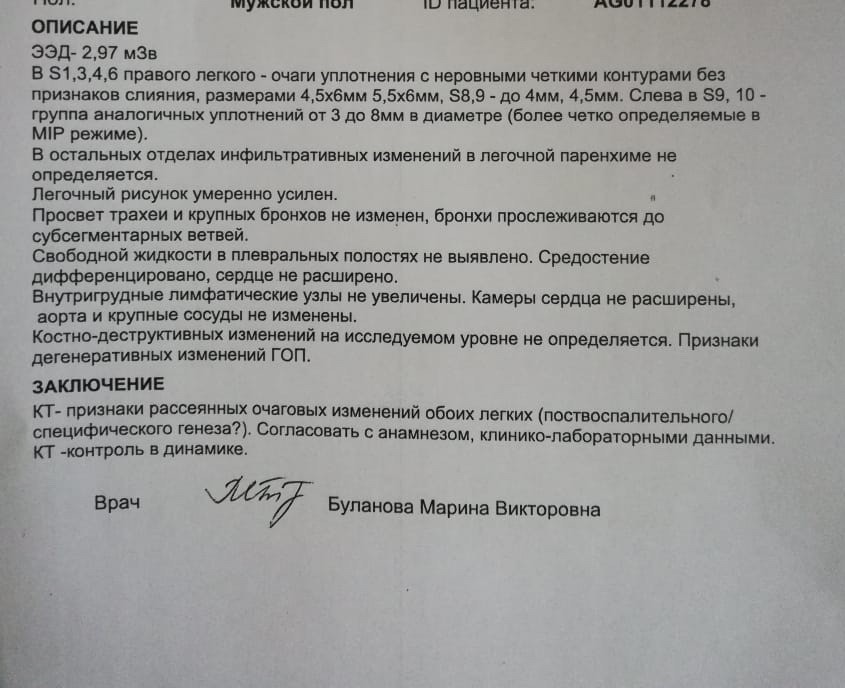

Фотографии и снимки КТ легких без контрастных веществ

Раздел: Визуальный дайджест